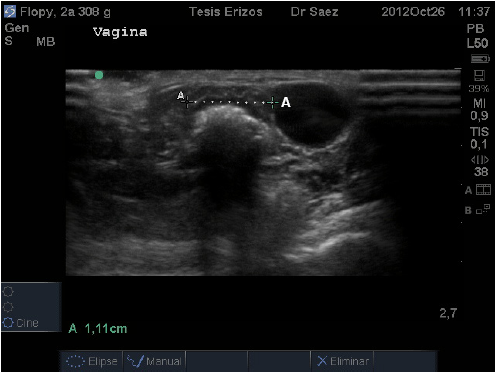

La vagina fue la primera porción en visualizarse y encontrándose en ella dos segmentos distintos, evaluados en corte transverso. El primero de ellos corresponde a una estructura tubular, hipoecoica, de granulado fino y homogéneo (FIG. 1). El segundo segmento, craneal al anterior, corresponde a una estructura con forma de óvalo plano, donde, en algunas ocasiones, fueron diferenciables tres capas: siendo la más interna hiperecoica que correspondería a presencia de mucus intraluminal, la banda media hipoecoica y la más externa hiperecoica (FIG. 2).

En algunos individuos se visualizó una región hipo o anecoica, la que correspondería a líquido presente en el interior del lumen, lo que en pequeñas cantidades podría considerarse como normal. Estos segmentos descritos corresponderían a vagina media y alta, respectivamente. La no visualización de la tercera porción de la vagina, correspondiente a la vagina baja, indicaría que este segmento se encontraría intrapélvico, lo que impediría su evaluación mediante ecografía. La diferencia de forma y diámetro entre los segmentos medio y alto de la vagina, esquematizados también por Reeve [11], podría deberse a que éste órgano, al estar formado por paredes musculares y no presentar contenido, como por ejemplo una gestación, que haga mantener su forma tubular, pasa a colapsarse y formar un óvalo plano.